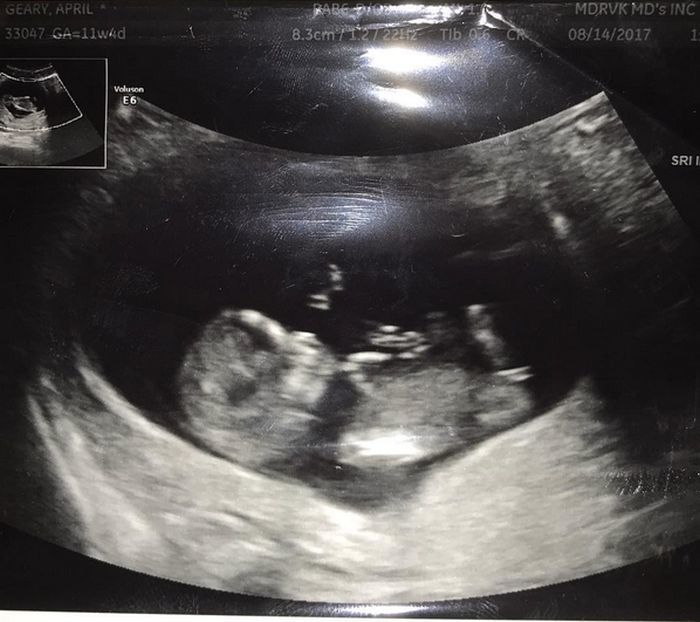

La doar câteva luni după ce s-a aflat că se va separa de Paula Patton, Robin Thicke (40 de ani) a început să se întâlnească cu modelul April Love Geary (22 de ani), iar acum cei doi sunt în culmea fericirii după ce au aflat că vor deveni părinţi. Noua iubită a cântăreţului a postat pe contul ei de Instagram prima ecografie, alături de mesajul: „Robin şi cu mine suntem foarte încântaţi să vă anunţăm că aşteptăm un copil. Data când va veni pe lume este 1 martie, ziua de naştere a lui Alan (tatăl lui Robin)”.